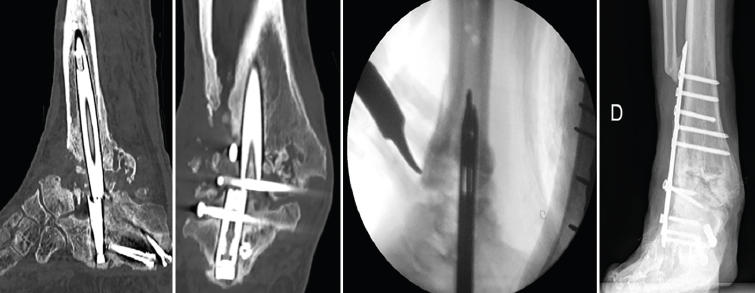

Figura 2. Agujas guías curvadas de revisión para la extracción de clavos rotos.

La reintervención se llevó a cabo a los 18 meses de la primera cirugía. En primer lugar, a través del punto de entrada plantar, se fijó el extremo distal del clavo con el sistema de extracción y se retiró el tornillo de bloqueo calcáneo. A continuación, se extrajo el tornillo proximal de la tibia y el astragalino extruido. Para la extracción del fragmento proximal del clavo, a través de la luz del clavo se introdujeron 2 guías con punta curvada, diseñadas para la extracción de los clavos de fémur rotos, enganchando la parte proximal del mismo y procediendo a su retirada (Figura 2). Se realizó un nuevo fresado del canal medular con el sistema RIA (reamer/irrigator/aspirator) (DePuy Synthes) y se colocó un clavo con una longitud y un diámetro mayores (210 y 13 mm, respectivamente). Mediante abordaje percutáneo se colocó el injerto en pasta ósea que obtuvimos con el sistema RIA a nivel tibiotalar, sin legrado de las superficies articulares. Se tomaron muestras intraoperatorias para cultivos bacterianos, que fueron negativos.